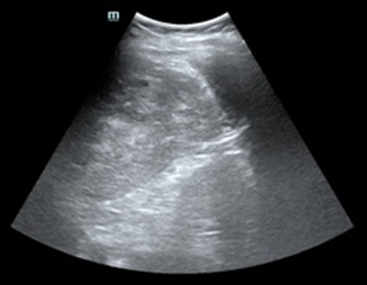

Tras varias horas en observación el paciente comienza con tendencia a la hipotensión. Permanece en observación y monitorización persistiendo hipotensión arterial con buena ventilación bilateral en la auscultación pulmonar. En la exploración abdominal presenta dolor y defensa a la palpación profunda en hipocondrio izquierdo. Se realiza Ecografía clínica a pie de cama del paciente descartando hemoneumotótax y derrame pericárdico; al explorar el abdomen se objetiva líquido libre en espacio de Morrison y eje espleno renal, con imagen compatible con rotura del parénquima esplénico. Gasométricamente se objetiva anemización con caída de cifras de Hb de 15,7 g/dl en análisis inicial a 13,8 g/dl. Se solicitan pruebas cruzadas, se reservan hemoderivados y se contacta con cirugía para traslado del paciente a quirófano.